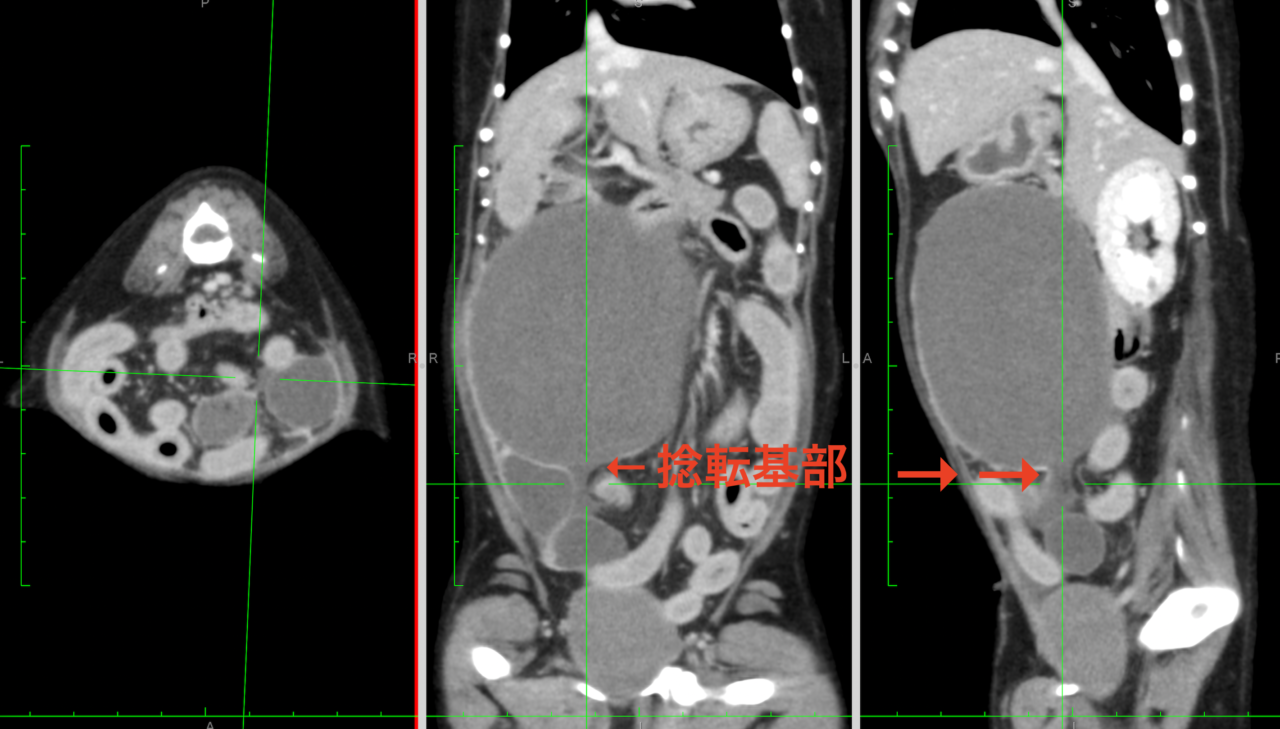

画像診断:特徴的な所見は述べらていませんが、CTで子宮の捻転基部が観察されました。

本症例は子宮水腫に続発した捻転と考えられました。ちいさな体で頑張ってくれました。